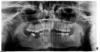

omik Опубликовано 20 июля, 2012 Поделиться Опубликовано 20 июля, 2012 Подскажите, пожалуйста, какие есть варианты исправления ситуации. Справа внизу мне лет в 12-ть удалили зуб. Сейчас мне 32. Хотела бы поставить имплант. В ветке хирургов посоветовали следующее: "надо выправлять заваленную 7ку, возможно действительно 2 имплантата вместо 6го, ну и внедрять и спиливать верхний 6й зуб. " Как можно выправить 7-ку? Это лечение брекетами или еще какие-либо варианты? Долго ли это? (быстрый поиск дает 12-18 месяцев) Как внедрят 6-ку? Нельзя ли поставить имплант внизу и он будет давить на 6-ку при жевании и она выправиться? (подозреваю, что не всё так просто... ) Спасибо заранее за советы. Ссылка на комментарий

Yana guapa Опубликовано 20 июля, 2012 Поделиться Опубликовано 20 июля, 2012 можно и брекетами (чтобы повернуть 7 зуб). можно и съемной аппаратурой. обычной пластинкой с накусочной площадкой. в месте, где отсутствует 6зуб - будет пластмасса. 6 верхний будет с ней контактировать и вколачиваться. занимает этот процесс не меньше 6 месяцев. (это зависит еще на сколько выдвинулась 6 верхний, надо в прикусе смотреть).А на имплант накусывать и вколачивать 6 верхний нельзя!!! Ссылка на комментарий